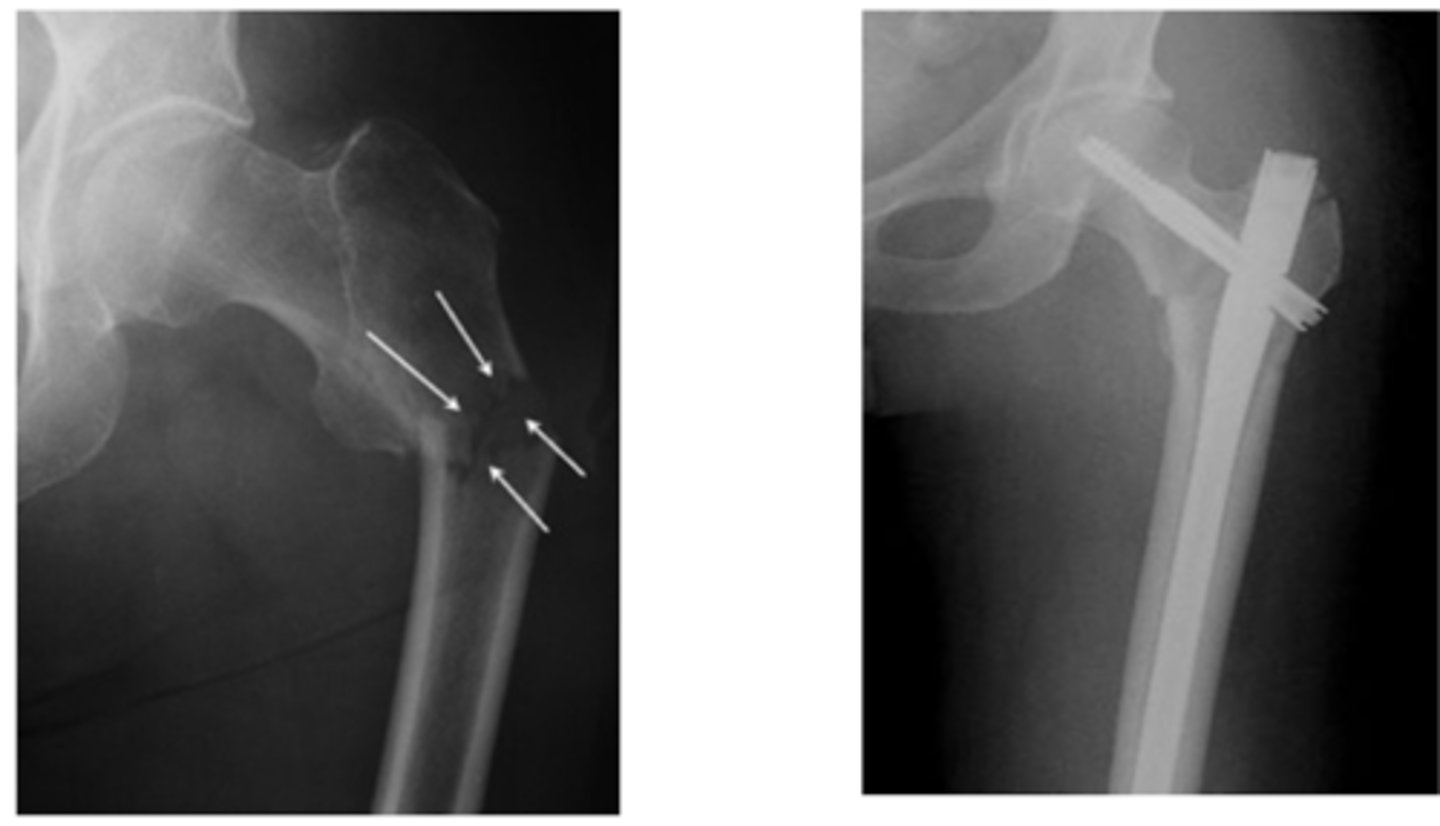

hip dysplasia on the Left photo

the L hip is worse than the R hip

very acute center edge angle

periacetabular osteotomy

used for hip dysplasia. break femur and pelvis, rotate them to provide greater joint angle

SCFE

percutaneous pinning for SCFE

intertrochanteric fx

intertrochanteric fx

Comminuted intertrochanteric fracture. There is a fracture from the greater to the lesser trochanter (blue arrow). There are separate fragments of the greater trochanter (white arrow) and lesser trochanter (red arrow). There is varus deformity (white line) of the femoral shaft.

subtrochanteric fx

subtrochanteric fx